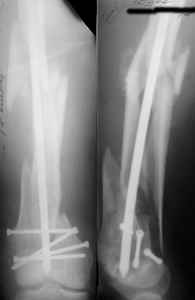

I presented a series of ~25 such cases at EuroTrauma'2004. Many cases were discussed here. I attach am example. Look also recent cases at http://www.hwbf.org/hwb/conf/alex58/scfx.htm,

http://www.hwbf.org/hwb/conf/alex63/alex63.htm

KEMMD> B. Fixation loosening: distal cutting of the nail, non-unions do happen

KEMMD> (cases attached).

The nail can be unlocked in the proximal fragment to prevent it.